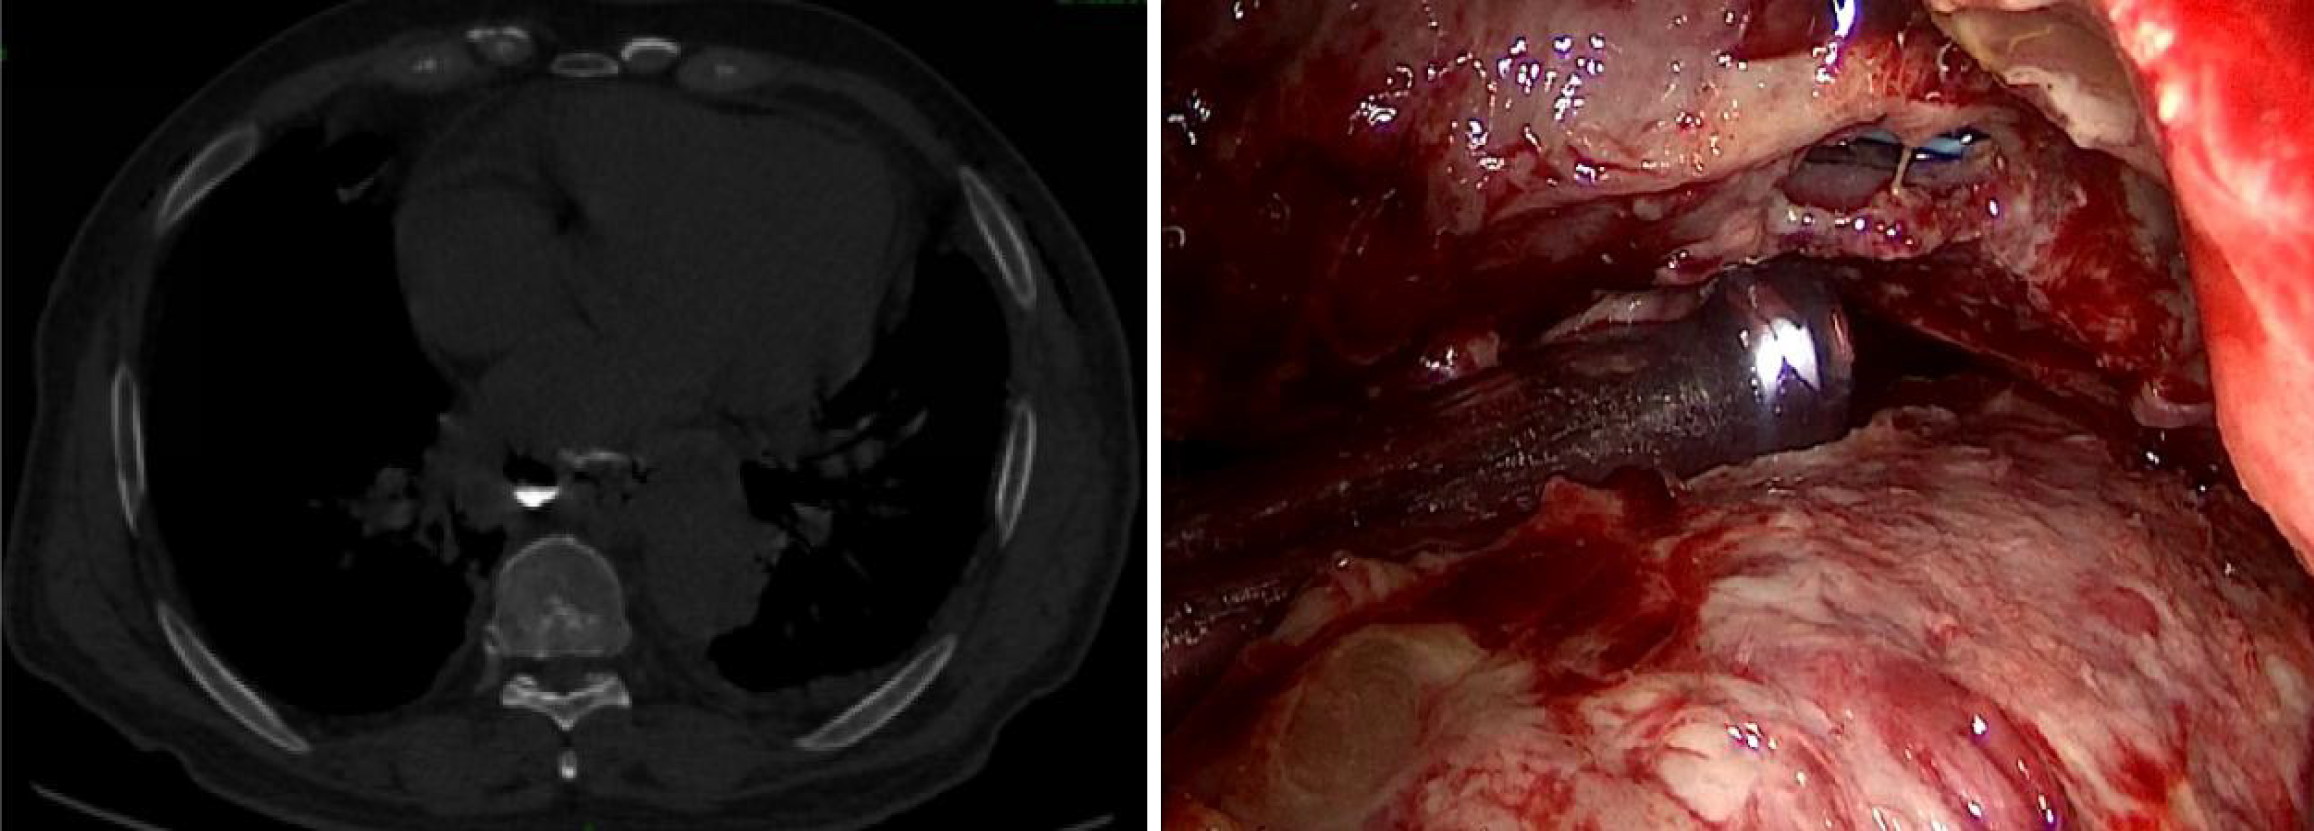

Figure 1 Enhanced computed tomography scan and chest enhanced magnetic resonance imaging.

A: Showing a giant posterior mediastinal tumor with a fatty component; B: Showing the tumor extensively involving the esophagus. There was still a small gap between the tumor and the esophagus.